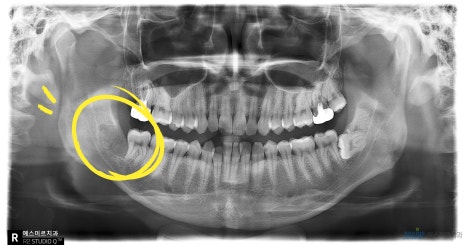

오른쪽 아래 완전매복사랑니 발치 전 후